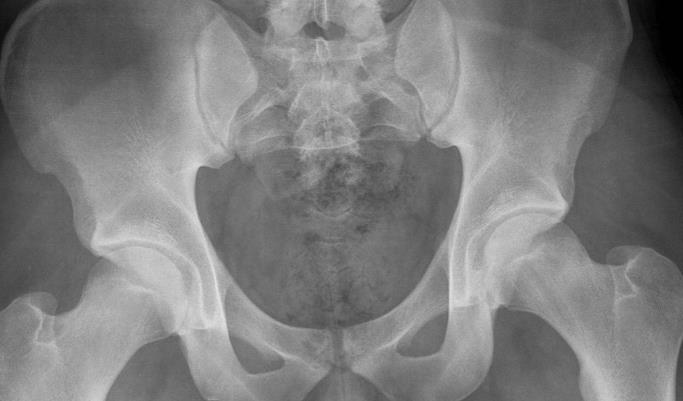

꼬리뼈

꼬리뼈는 미골, 미저골 이라고 부르는데요, 영어로는 coccyx 라고 표기 합니다.

꼬리뼈는 원래 사람은 꼬리가 있었지만 점점 진화하면서 이 부분이 퇴화되어 그 흔적으로 꼬리뼈라는게 남아 이름이 붙여졌다고 알려져있죠.